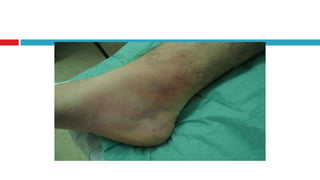

Tromboflebitis superficial Inflamación de una vena, justo debajo de la superficie de la piel, como resultado de un coágulo sanguíneo. Esta condición puede ocurrir después del uso reciente de un método intravenoso (IV) o después de un traumatismo en la vena.  Síntomas pueden ser dolor y sensibilidad a lo largo de la vena, endurecimiento(sensacion cuerda)  Los síntomas se resuelven de una a dos semanas, pero la dureza de la vena puede permanecer por mucho más tiempo.

Las venas superficiales están inflamadas y dilatadas, lo cual causa la hipopigmentaci ó n   Tromboflebitis superficial